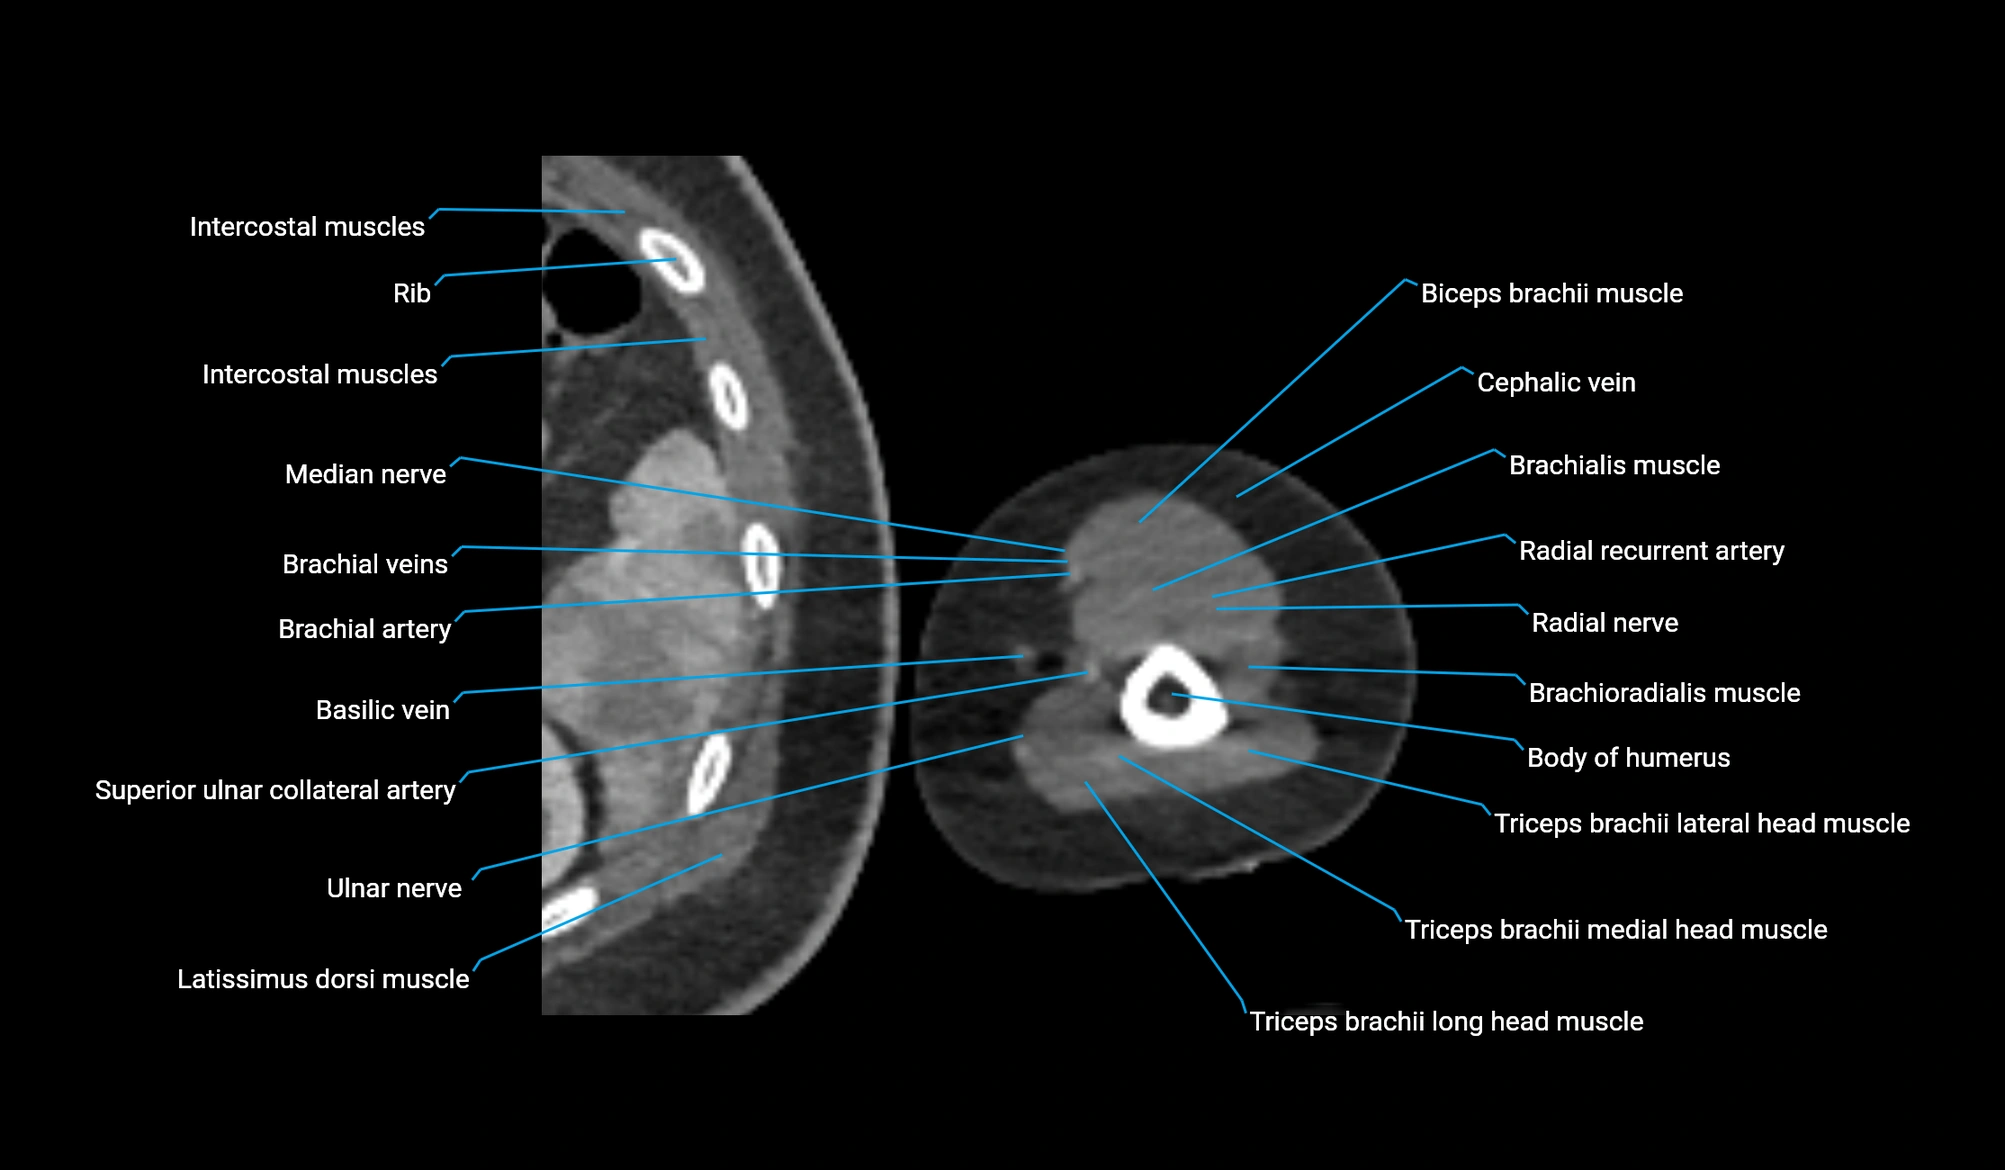

- Body of humerus

- Brachial artery

- Brachialis muscle

- Brachioradialis muscle

- Cephalic vein

- Lateral head of triceps brachii muscle

- Long head of triceps brachii muscle

- Medial head of triceps brachii muscle

- Median nerve

- Radial nerve

- Radial recurrent artery

- Superior ulnar collateral artery

- Triceps brachii muscle